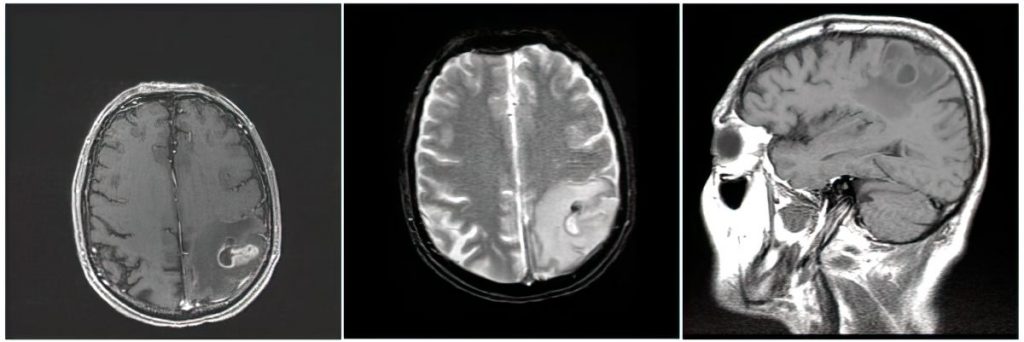

- It is high yield to be able to identify CNS abscess on MRI:

- An abscess will have internal restricted diffusion due to the presence of pus, with a smooth rim of enhancement and adjacent vasogenic edema.

- If multiple lesions are present, consider septic emboli.